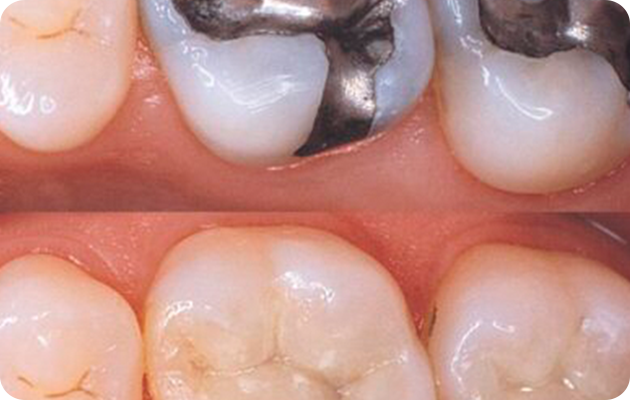

Composite Resin Fillings

• Material: Tooth-colored blend of plastic and glass.

• Pros: Blends naturally with your teeth; ideal for visible areas.

• Cons: Less durable than metal; may need replacement in 5–10 years.